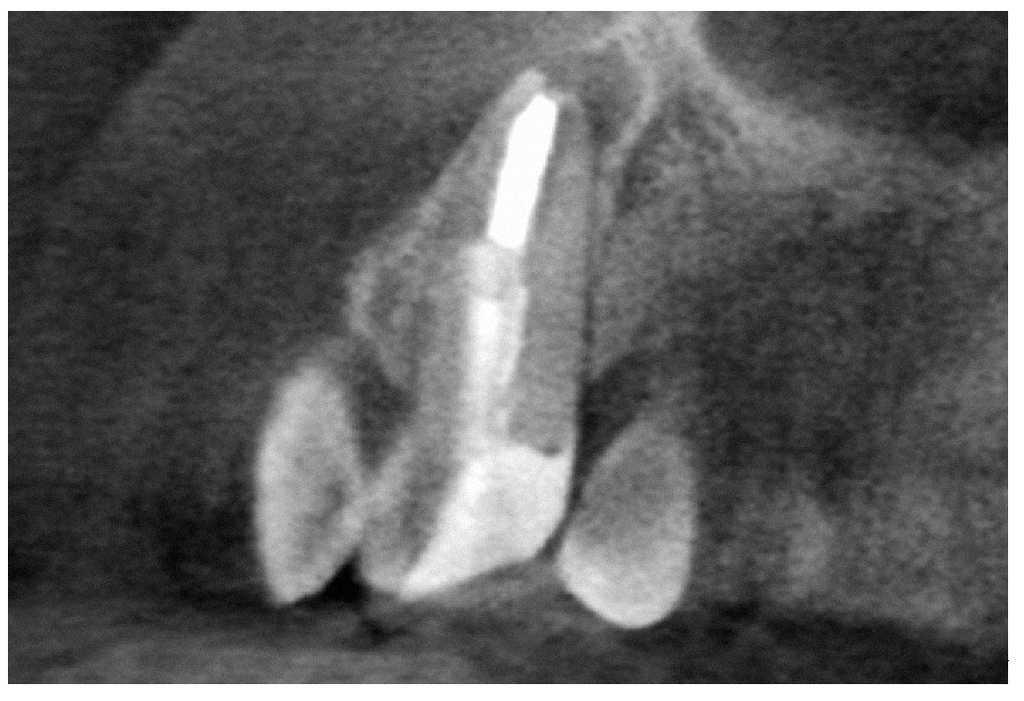

Figura 9a. Radiografía del diente 13 con perno metálico y periodontitis apical.

Figura 9b. La tomografía computarizada de haz cónico muestra la posición del perno en el conducto radicular desde mesial.